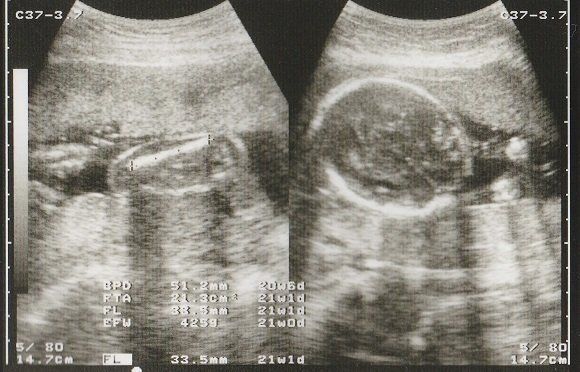

妊娠21週目のエコー写真 赤ちゃんが激しく動くようになる

FL(大腿骨長)が30mmを超えました。人体で一番長い骨である大腿骨の長さを測って、赤ちゃんの成長をチェックしています。

妊娠6カ月になると、おなかも多くなり、赤ちゃんの動きも激しくなってきました。